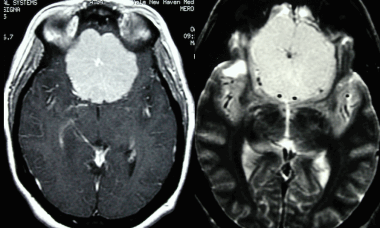

Менингиома лобной доли: КТ-картина. После введения контрастного вещества виден характерный вид «колеса со спицами» в структуре слабо контрастируемой опухоли. Несмотря на то, что данный паттерн чаще наблюдается при ангиографии, он также отмечается на томографических изображениях.

МРТ того же пациента, выполненная после предыдущей КТ: аксиальное Т1-взвешенное изображение после введения гадолиния и аксиальное Т2-взвешенное изображение. Видна крупная менингиома лобной области, расположенная срединно, со специфическим паттерном «колеса со спицами».